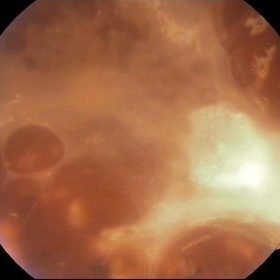

Proliferative Diabetic Retinopathy

Color fundus photography of a 62- year-old diabetic patient. Severe fibrous proliferations with traction retinal detachment can be seen. Pars plana vitrectomy was preformed on that eye.

Photographer: Marko Lukic, MD

Imaging device: Zeis Visucam Lite 2

Condition/keywords: neovascularization (NV)